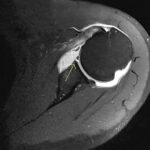

MR Arthrogram Scan

Advanced MR Arthrogram scan which is also known as joint analysis is offered by Medifyhome to diagnose joint-related issues. An MR Arthrogram Scan is an MRI scan done with a contrast dye injected into the joint to give detailed images of cartilage, tendons, ligaments, and other soft tissues around the joint. This scan is especially beneficial in identifying such injuries or alterations that are invisible on normal MRI scans, thus, it becomes an essential tool of choice when determining for abnormality in the joint region that includes shoulder, hip, knee, and elbow. Whether it is pain, stiffness, or difficulty in moving, an MR Arthrogram Scan will be able to provide unrivaled insight into what may be the problem. Medifyhome arranges for experienced radiologists along with advanced facilities so that this test result comes timely and precisely. At Medifyhome, we strive to make the MR Arthrogram Scan experience as comfortable as possible with the convenience of easy appointment scheduling at an affordable price. Allow Medifyhome to take care of your comprehensive and quick diagnosis regarding joint health.